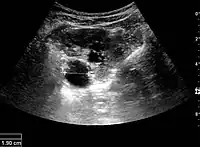

Figure 7. Advanced polycystic kidney disease with multiple cysts.[1]

Complex cysts can have membranes dividing the fluid-filled center with internal echoes, calcifications or irregular thickened walls. The complex cyst can be further evaluated with Doppler US, and for Bosniak classification and follow-up of complex cysts, either contrast-enhanced ultrasound (CEUS) or contrast CT is used (Figure 6). The Bosniak classification is divided into four groups going from I, corresponding to a simple cyst, to IV, corresponding to a cyst with solid parts and an 85–100% risk of malignancy.[1] In polycystic kidney disease, multiple cysts of varying size in close contact with each other are seen filling virtually the entire renal region. In advanced stages of this disease, the kidneys are enlarged with a lack of corticomedullary differentiation (Figure 7).[1]